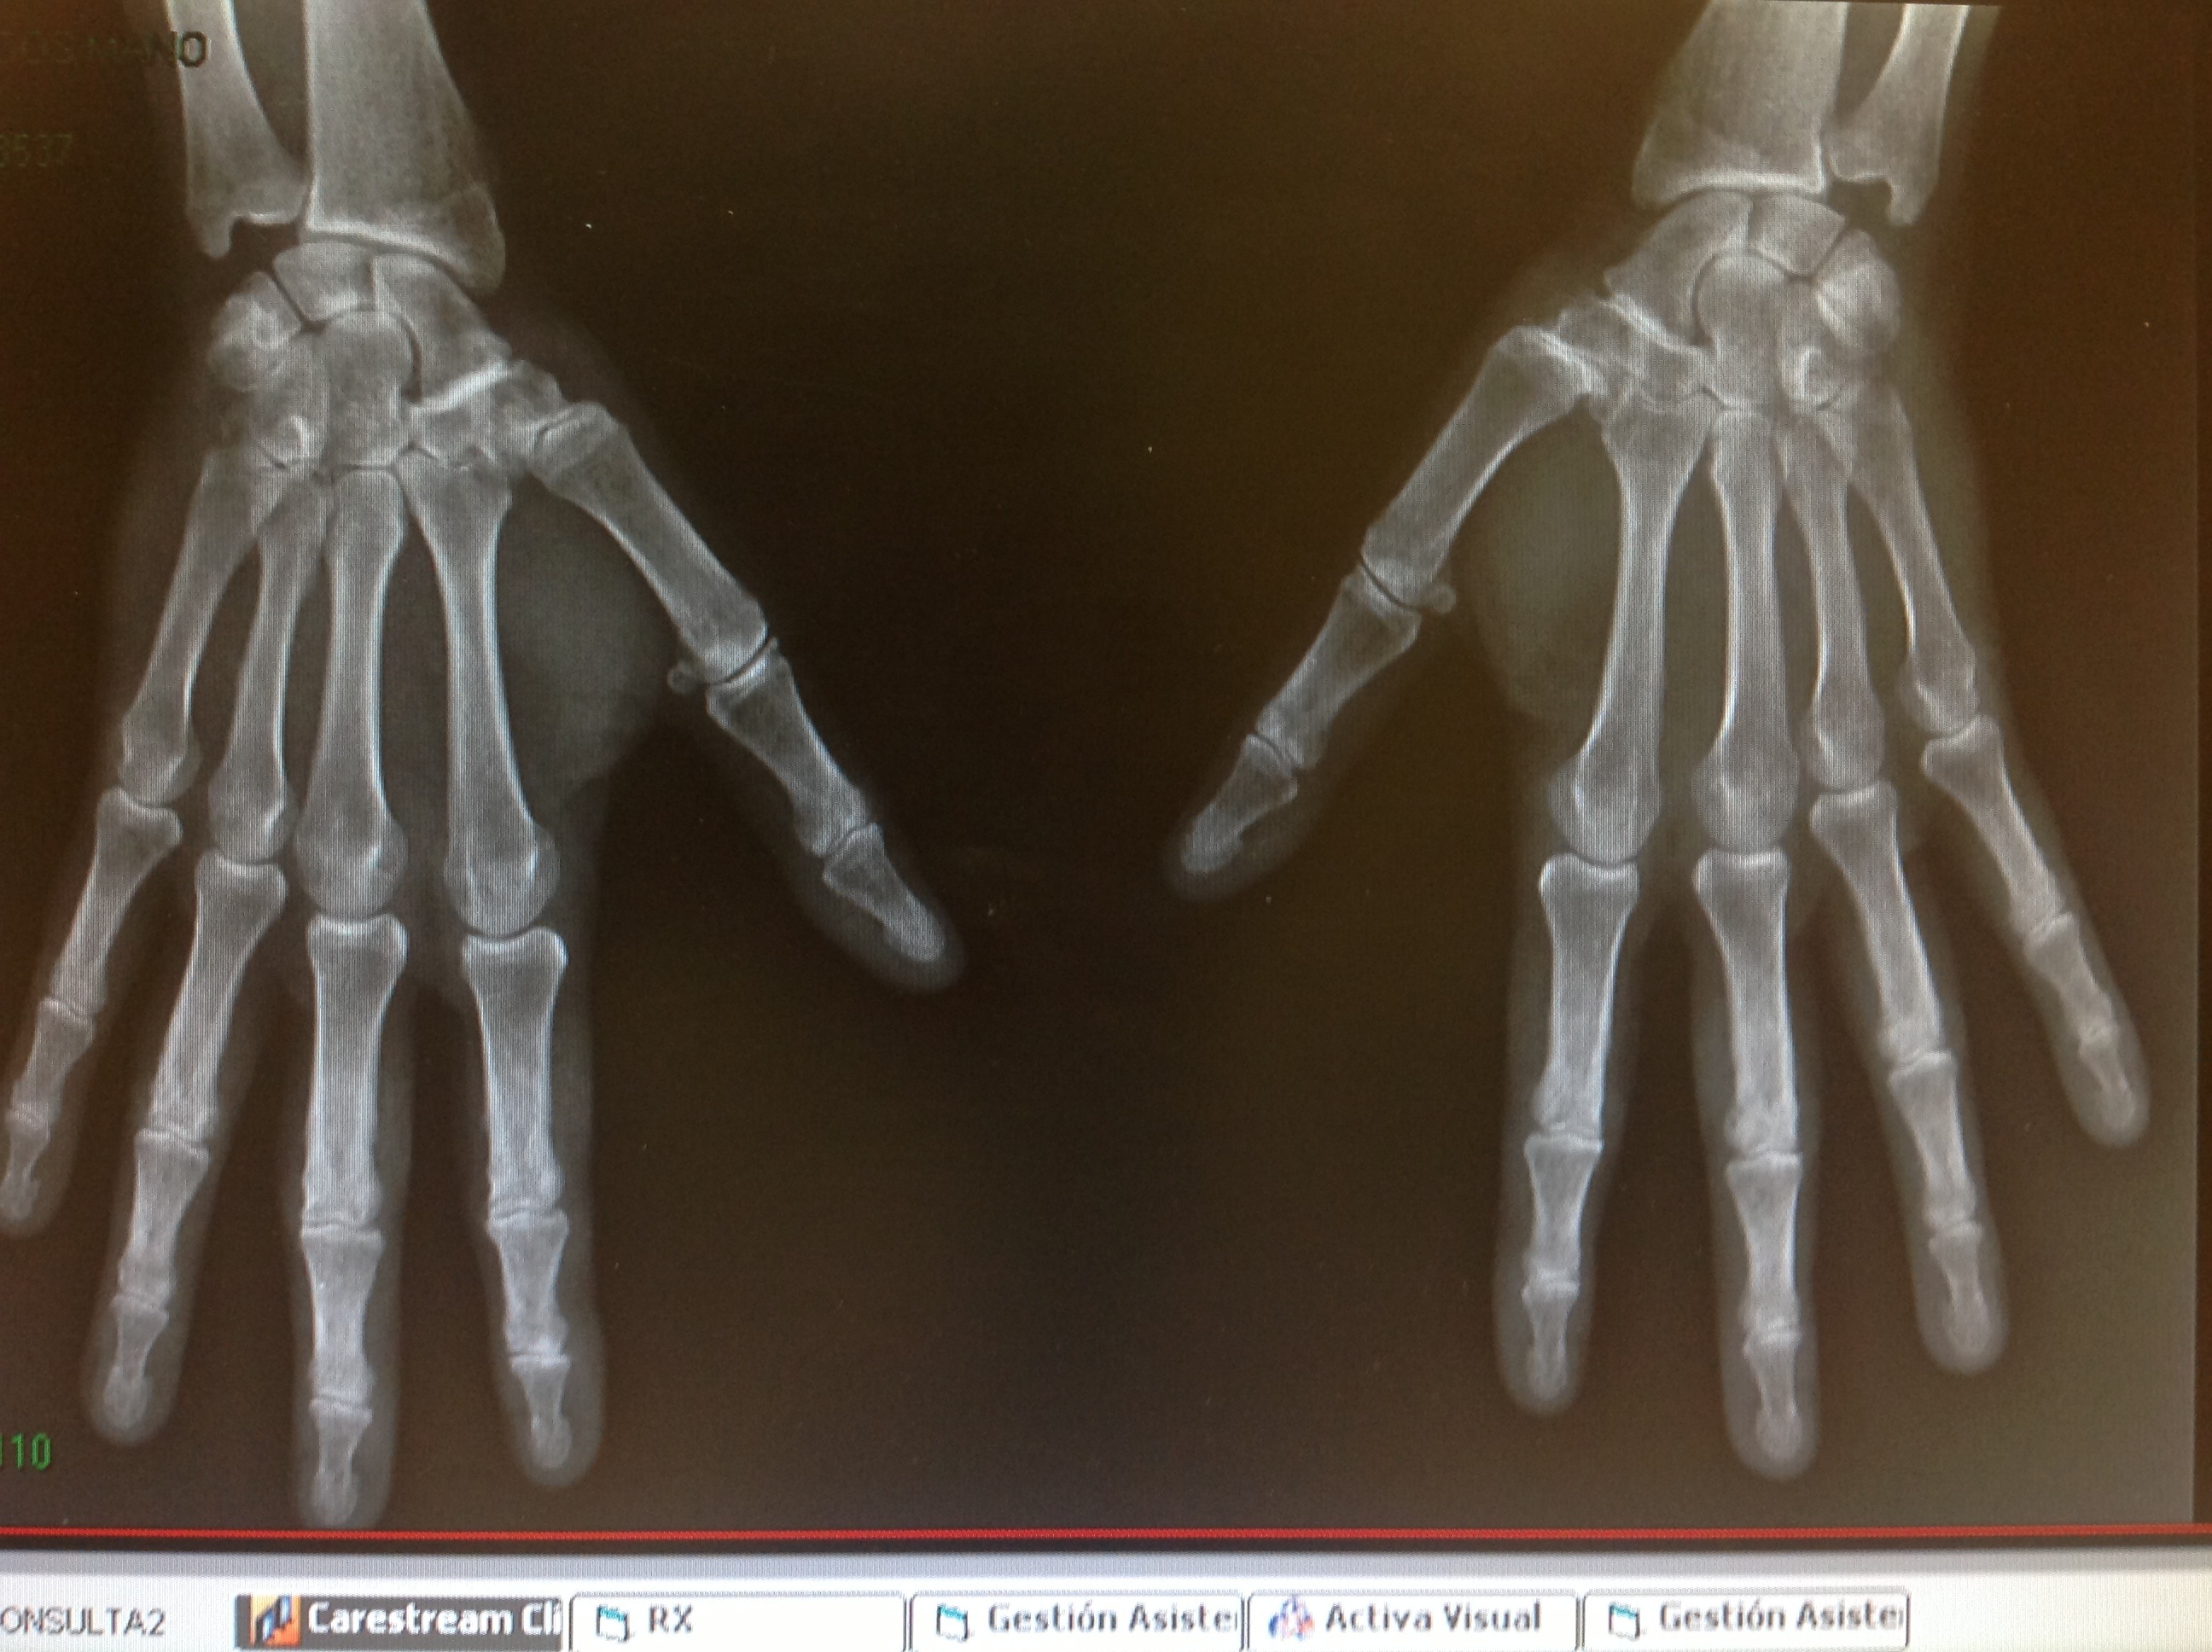

Cuando valoramos una proyección posteroanterior de la Mano , no estamos viendo una anteroposterior de la columna del pulgar sinó su perfil.

Tal como podéis valorar , a nivel de la articulación metacarpofalángica se dibuja bien el sesamoideo en perfil….. O sea que una posteroanterior de Mano es en realidad un perfil de la columna de pulgar.